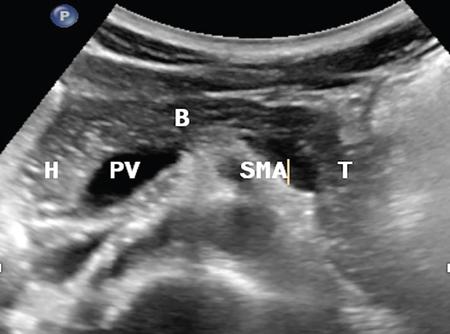

CROSS SECTIONAL ANATOMY OF ABDOMEN Satya Jha NORMAL ANATOMY OF ABDOMEN AND PELVIS Amandeep Singh The two major surfaces: The anterior and posterior layers of the coronary ligament converge on bare area (not covered by peritoneum). Its right and left margins form the right and left triangular ligaments. The right triangular ligament extends toward the diaphragm and separates right subphrenic space from right subhepatic space. The left triangular ligament gives tracts extending to the diaphragm and falciform ligament and does not compartmentalize the left subphrenic space. Ligamentum teres or the obliterated umblical vein is contained in falciform ligament which attaches the liver to anterior abdominal wall. The main portal vein, the proper hepatic artery and the common bile duct are contained within investing peritoneal folds of hepatoduodenal ligament at the porta hepatis (Fig. 7.2.2.1). Liver is divided into eight segments which are functionally independent and have their own vascular supply and biliary drainage. Arterial circulation: The branches of the hepatic artery accompanying the portal veins. Hepatic venous system: The right, middle, and left hepatic veins draining into IVC (Figs. 7.2.2.2 and 7.2.2.3). The gallbladder is a blind pear-shaped muscular membranous sac which is an embryologic derivative of the foregut, is a pouch lying along the undersurface of the liver. The gallbladder fossa is located in the plane of the interlobar fissure, which lies between the right and left hepatic lobes. Its major function is to store and concentrate bile which is produced by the liver. It measures approximately 4 cm in diameter when it is normally distended. Gallbladder is a smaller tubular structure in contracted state. The normal gallbladder wall thickness ranges from 1 to 3 mm. The gallbladder is divided into the fundus, body and neck. Infundibulum is present in the region of neck of the gallbladder, which is called the Hartmann pouch, where gallstones are usually impacted. Intrahepatic biliary radicles (IHBRs) scattered throughout the liver get confluent towards the hilum. They unite to form the right and left main hepatic ducts which further unite to form common hepatic duct (CHD) at the hilum. Common bile duct is formed by the union of cystic duct with common hepatic duct. The main pancreatic duct is joined with the common bile duct to form the ampulla of Vater at the major duodenal papilla (Figs. 7.2.2.4 and 7.2.2.5). Pancreas is located in anterior pararenal space of retroperitoneum anterior to perirenal (Gerota’s) fascia and posterior to parietal peritoneum. It is divided into head, uncinate process, neck, body and tail from right to left. Pancreas lies anterior to portal vein, which marks the point of transition between the body and neck. The region between head of pancreas and second and third parts of duodenum is known as the pancreatic groove. In postnephrectomy cases or with agenesis of kidney or ectopic kidney, pancreas moves posteriorly to partially fill in the empty renal fossa; its soft tissue density should not be mistaken for recurrent tumour. It is located in the pancreatic groove and is bounded superiorly by the duodenal bulb, laterally by second portion of duodenum, inferiorly by third portion of duodenum, medially by superior mesenteric vein and anterior to inferior vena cava. It is a wedge or wedge shaped lying posterior to superior mesenteric artery and vein. It is an imaginary junction between the head and body and lies directly over the junction of the splenic vein and superior mesenteric vein. It is located posterior to the lesser sac and anterior to the aorta, left adrenal gland, left kidney, and renal vessels and runs obliquely upward to the left of the superior mesenteric vessels. It is situated median to the colonic flexure and anterior to the left kidney. It is located in close proximity to the splenic hilum without a notable relation with the body of pancreas. It is seen anterior to the left kidney and median to the colonic flexure. The distal part of the tail passes between the peritoneal layers of the splenorenal ligament (Fig. 7.2.2.6 and 7.2.2.7).